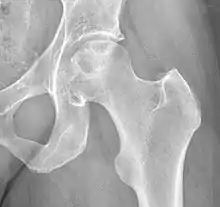

| X-ray of hip with femoral head osteonecrosis | |